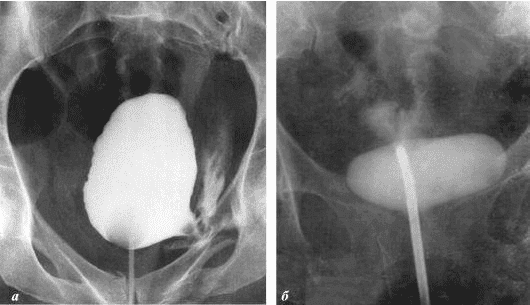

Ich möchte Ihnen ein paar Fotos zeigen, um zu zeigen, was im Urogenitalsystem und anderen Organen eines Mannes vor sich geht, der keinen Sex hat.

So sieht eine Entzündung der Prostata aus, die durch Stagnation der Spermien verursacht wird (wenn die Hoden nicht geleert werden). Eine anhaltende Entzündung führt zuerst zu einem Prostataadenom und dann zu Krebs. Dies ist eine unvermeidliche Folge von Prostatitis, daher wird es als "Krankheit der älteren Generation" bezeichnet.